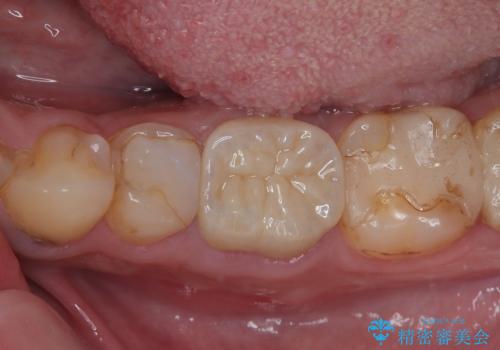

- 奥歯の歯肉から定期的に膿が出てくるとのことで来院された患者様です。

レントゲン写真などの診察を行った結果、根管治療が必要であったため、現在のクラウンを除去し、根管治療を行うこととしました。

根管治療後は症状を確認し、速やかにオールセラミッククラウンにて補綴治療を行うこととしました。